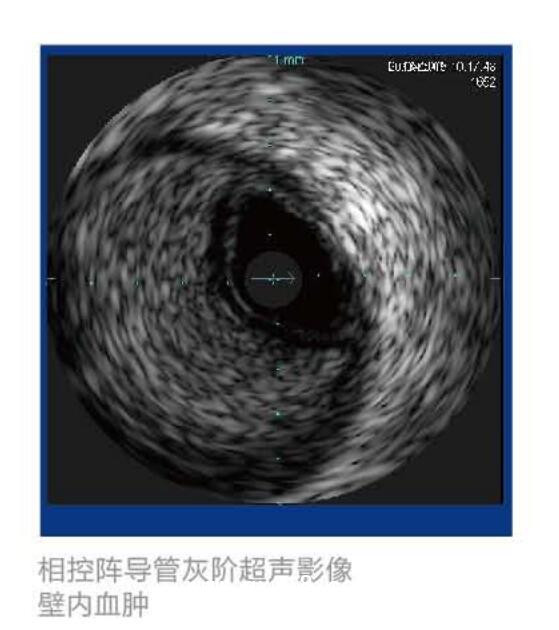

美國(guó)VOLCANO血管內(nèi)超聲波診斷儀 S5產(chǎn)品說(shuō)明: